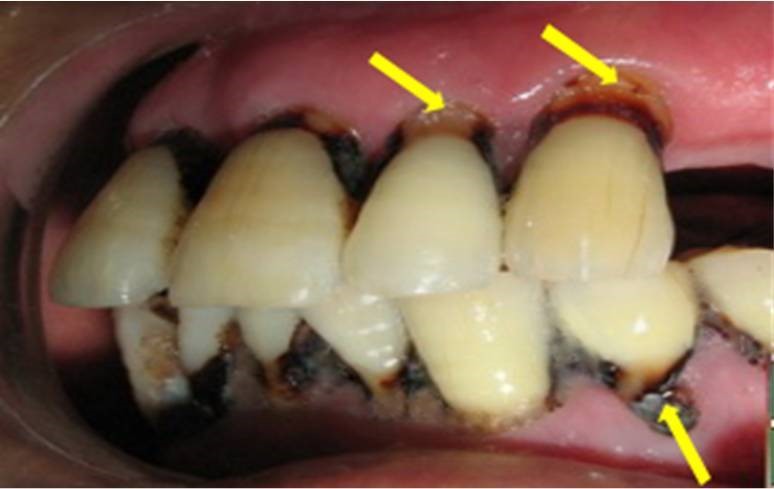

目前中老年人的牙齿疾病主要体现在四大方面:牙齿磨耗、牙龈萎缩、龋齿、牙周病。龋齿和牙周病可以说是中老年牙缺失的两大“元凶”。

(根面龋)                                                                                                           (牙周病